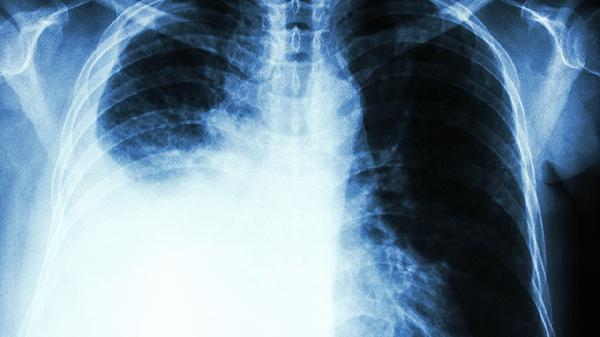

肺癌这个"沉默杀手"正悄悄逼近越来越多的人。最近体检中心的数据显示,肺部结节检出率比五年前翻了一番。别以为只有老烟枪才会中招,那些看似无害的生活习惯,可能正在摧毁你的肺功能。